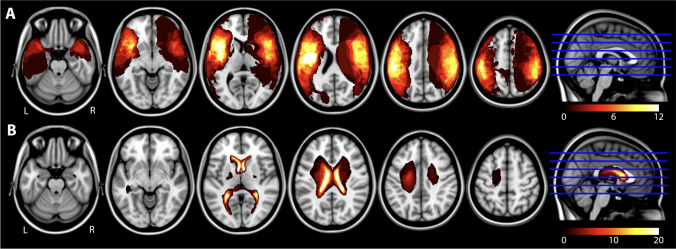

Lesion overlap maps for each of the two stroke groups are illustrated in Fig. 2 where brighter areas reflect greater overlap among participants. Group lesion sizes are reported in Table 1.

Fig. 2.

Lesion overlay maps for the (A) arterial ischemic stroke (AIS) and (B) periventricular venous infarction (PVI) patient groups. Brighter colours represent larger numbers of participants with a lesion in that brain area